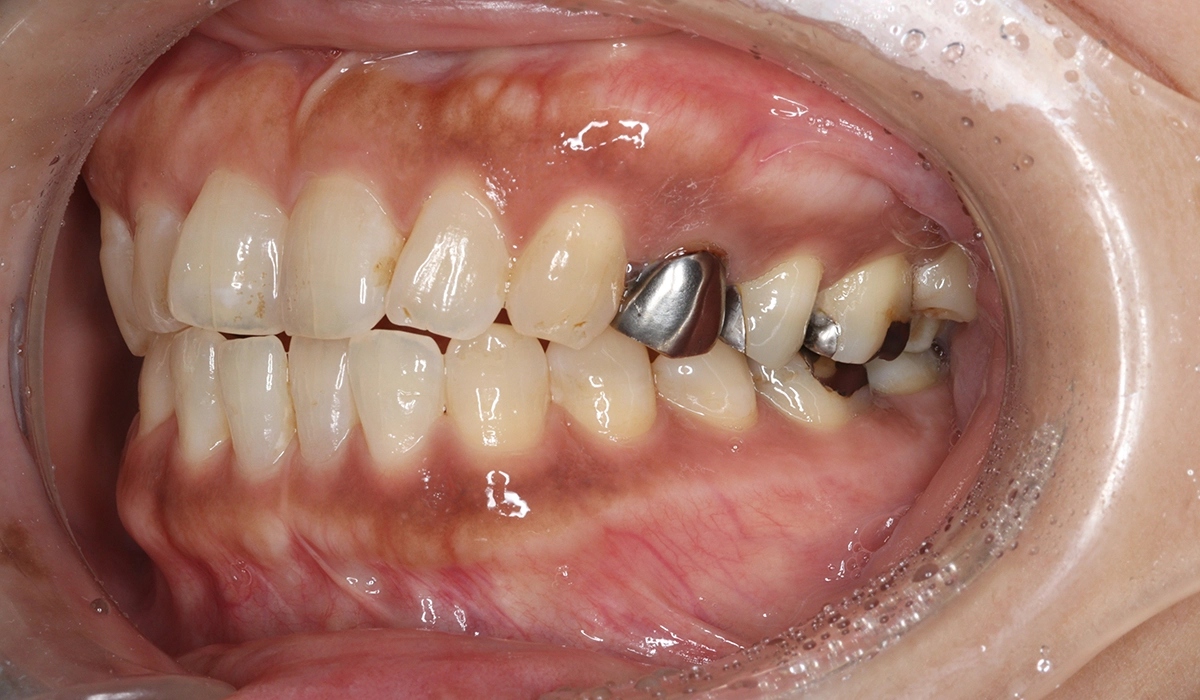

術前:右側